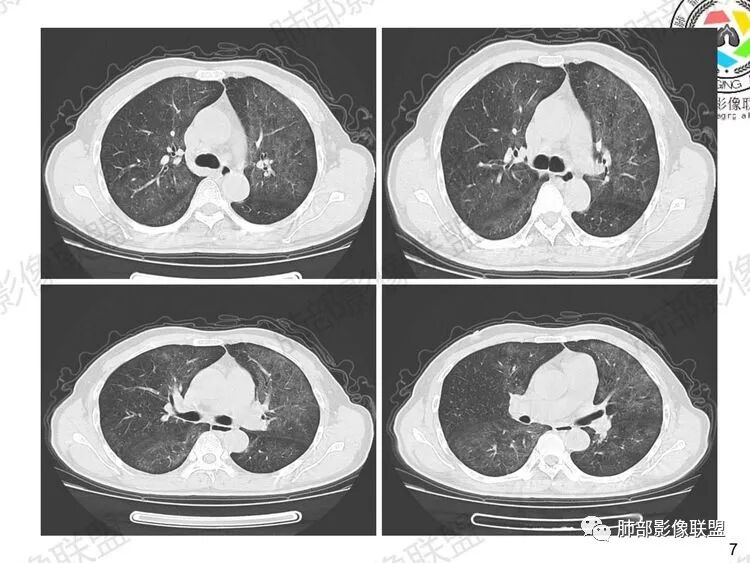

早期:孢子菌滋养体吸入附在肺泡壁上,破坏I型肺泡上皮细胞的细胞膜,使细胞坏死及毛细血管通透性增加。液体渗出到肺泡腔内,病灶主要位于肺泡内,肺泡腔密度增高,间质这时受累相对轻,因此早期为渗出期,病变由中心向外周分布,表现为两肺多发对称性的弥漫斑点状、粟粒状阴影,边界清楚。

中期:孢子菌在肺泡腔内大量繁殖,引起炎性渗出及肺泡上皮增生,肺泡液内含有滋养体的嗜酸性渗出物及纤维蛋白和脱落的上皮细胞,Ⅱ型肺泡上皮细胞增殖修复受损的肺泡毛细血管间膜,肺间质内巨噬细胞、浆细胞和淋巴细胞增殖导致间质性肺炎,就是说有肺泡腔的密度增高,也有间质的增厚,整个肺受累区域密度都增高,形成以肺门为中心双侧对称的弥漫性磨玻璃样改变,胸膜下较少累及,呈典型的月弓征,采用积极的对症治疗后,大多数病变可吸收消失。

注意肺孢子菌肺炎的肺部影像看上去比较“干”,不会呈现重力趋势。肺血管影及支气管影都比较清楚,尤其是含气支气管影,常常会衬托得格外清晰。

1、双肺从中心向外周对称性弥漫分布的磨玻璃密度影,无重力分布特点

2、中内带分布为主,胸膜下较少受累,可见月弓征